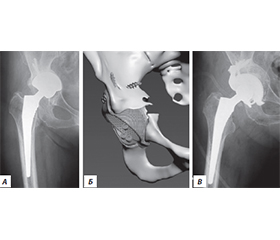

Актуальність. Ендопротезування кульшового суглоба сьогодні є одним із найбільш поширених і водночас ефективних методів лікування. Проте у віддалені терміни після операції виникає проблема розвитку нестабільності елементів протеза, що потребує повторних оперативних втручань, які належать до категорії складних і технічно трудомістких. Мета дослідження: на основі власного досвіду ревізійного ендопротезування кульшового суглоба та даних літератури обговорити питання планування і вибору тактики оперативного лікування для покращення результатів. Матеріали та методи. Було проаналізовано результати 146 ревізійних ендопротезувань кульшового суглоба у пацієнтів з асептичною нестабільністю елементів протеза за 11 років (2012–2022). Серед обстежених було 93 жінки та 53 чоловіки, вік пацієнтів коливався від 24 до 82 років (середній вік становив 64,5 року). Функціональне відновлення хворих оцінювали за шкалою Harris Hip Score. Результати. Нестабільність ацетабулярного компонента й ніжки протеза спостерігали у 34 пацієнтів, лише ацетабулярного компонента — у 48 осіб, лише ніжки — у 32 хворих, вивих протеза — у 9, стирання поліетиленового вкладиша — у 5, перелом керамічної головки — у 2, перелом ніжки протеза — в 1, перипротезні переломи — у 15 пацієнтів. Середній показник шкали Harris Hip Score становив 79,3 бала (95% довірчий інтервал: 73,9–84,7). Відмінні або добрі результати досягнуто у 52,8 % пацієнтів, задовільні — у 29,5 %, незадовільні — у 17,8 %. Загальна частота післяопераційних ускладнень становила 7,53 %. Висновки. У ревізійному ендопротезуванні доцільно віддавати перевагу безцементним системам фіксації з обов’язковим застосуванням кісткової пластики при дефіциті кісткової тканини. Найбільш ефективними виявилися ацетабулярні чашки з покриттям екструдованим титаном, а також ревізійні й індивідуально виготовлені конструкції. При ревізії стегнового компонента ніжка Wagner продемонструвала стабільні клінічні результати та надійність фіксації.

Background. Hip arthroplasty is one of the most common and effective surgical methods of treatment. However, over time, the problem of prosthetic component instability arises, requiring revision procedures. The aim was to analyze own experience of revision hip arthroplasty and literature data, with a focus on planning and surgical strategy to improve outcomes. Materials and methods. We analyzed the results of 146 revision hip arthroplasties performed in patients with aseptic prosthetic component instability in 2012–2022. The study cohort included 93 women and 53 men, aged 24–82 years (mean age 64.5). The functional recovery of patients was assessed using the Harris Hip Score scale. Results. Instability of both the acetabular component and femoral stem was observed in 34 patients; isolated acetabular component instability in 48; isolated femoral stem instability in 32; prosthetic dislocation in 9; polyethylene liner wear in 5; ceramic head fracture in 2; femoral stem fracture in 1; and periprosthetic fractures in 15 patients. The mean Harris Hip Score was 79.31 units (95% CI: 73.9–84.7). More than half of the patients (52.8 %) achieved excellent or good results, 29.5 % — satisfactory, and 17.8 % — unsatisfactory. The overall rate of postoperative complications was 7.53 %. Conclusion. In revision hip arthroplasty, preference should be given to cementless fixation systems with mandatory bone grafting in cases of bone deficiency. The most effective implants were acetabular cups with extruded titanium coating, as well as revision and custom-made components. In femoral component revisions, the Wagner stem demonstrated stable clinical outcomes and reliable fixation.